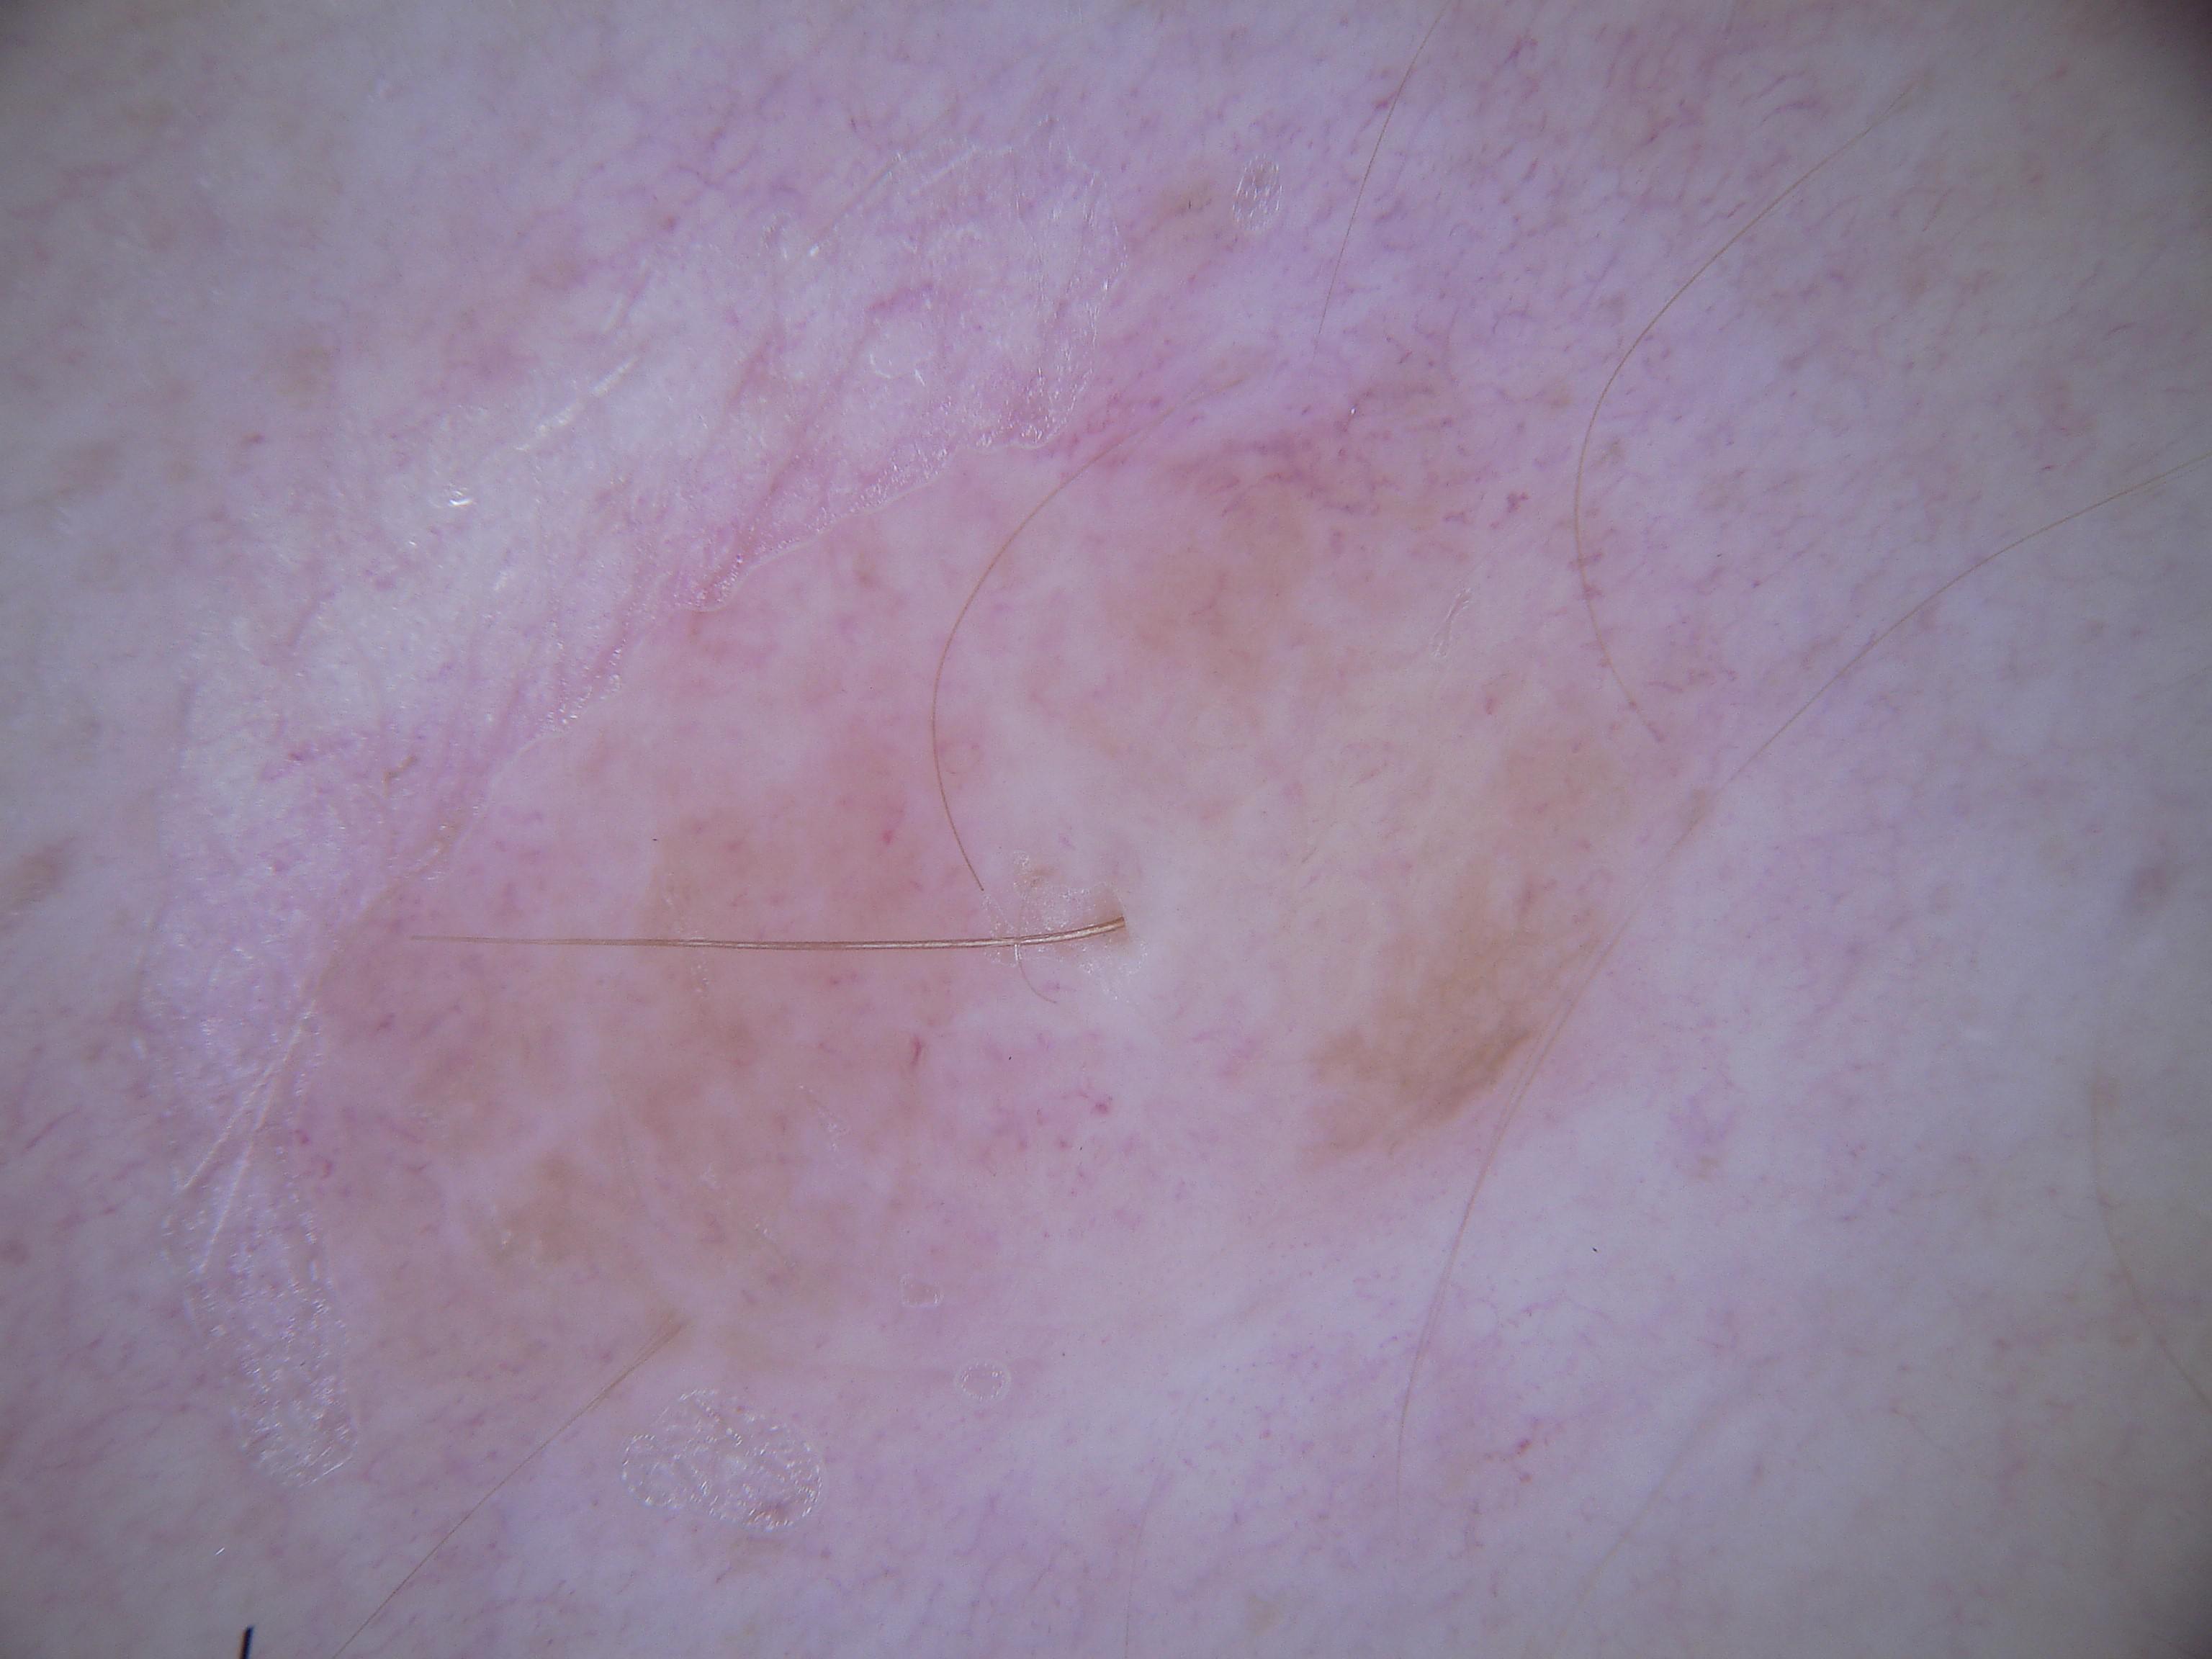

{

"age_approx": 60,

"anatom_site_general": "lower extremity",

"concomitant_biopsy": true,

"dermoscopic_type": "non-contact polarized",

"diagnosis_1": "Malignant",

"diagnosis_2": "Malignant melanocytic proliferations (Melanoma)",

"diagnosis_3": "Melanoma in situ",

"diagnosis_4": "Melanoma in situ, associated with a nevus",

"diagnosis_confirm_type": "histopathology",

"family_hx_mm": false,

"image_type": "dermoscopic",

"mel_thick_mm": "0.00",

"melanocytic": true,

"patient_id": "IP_7903739",

"personal_hx_mm": true,

"sex": "male"

}